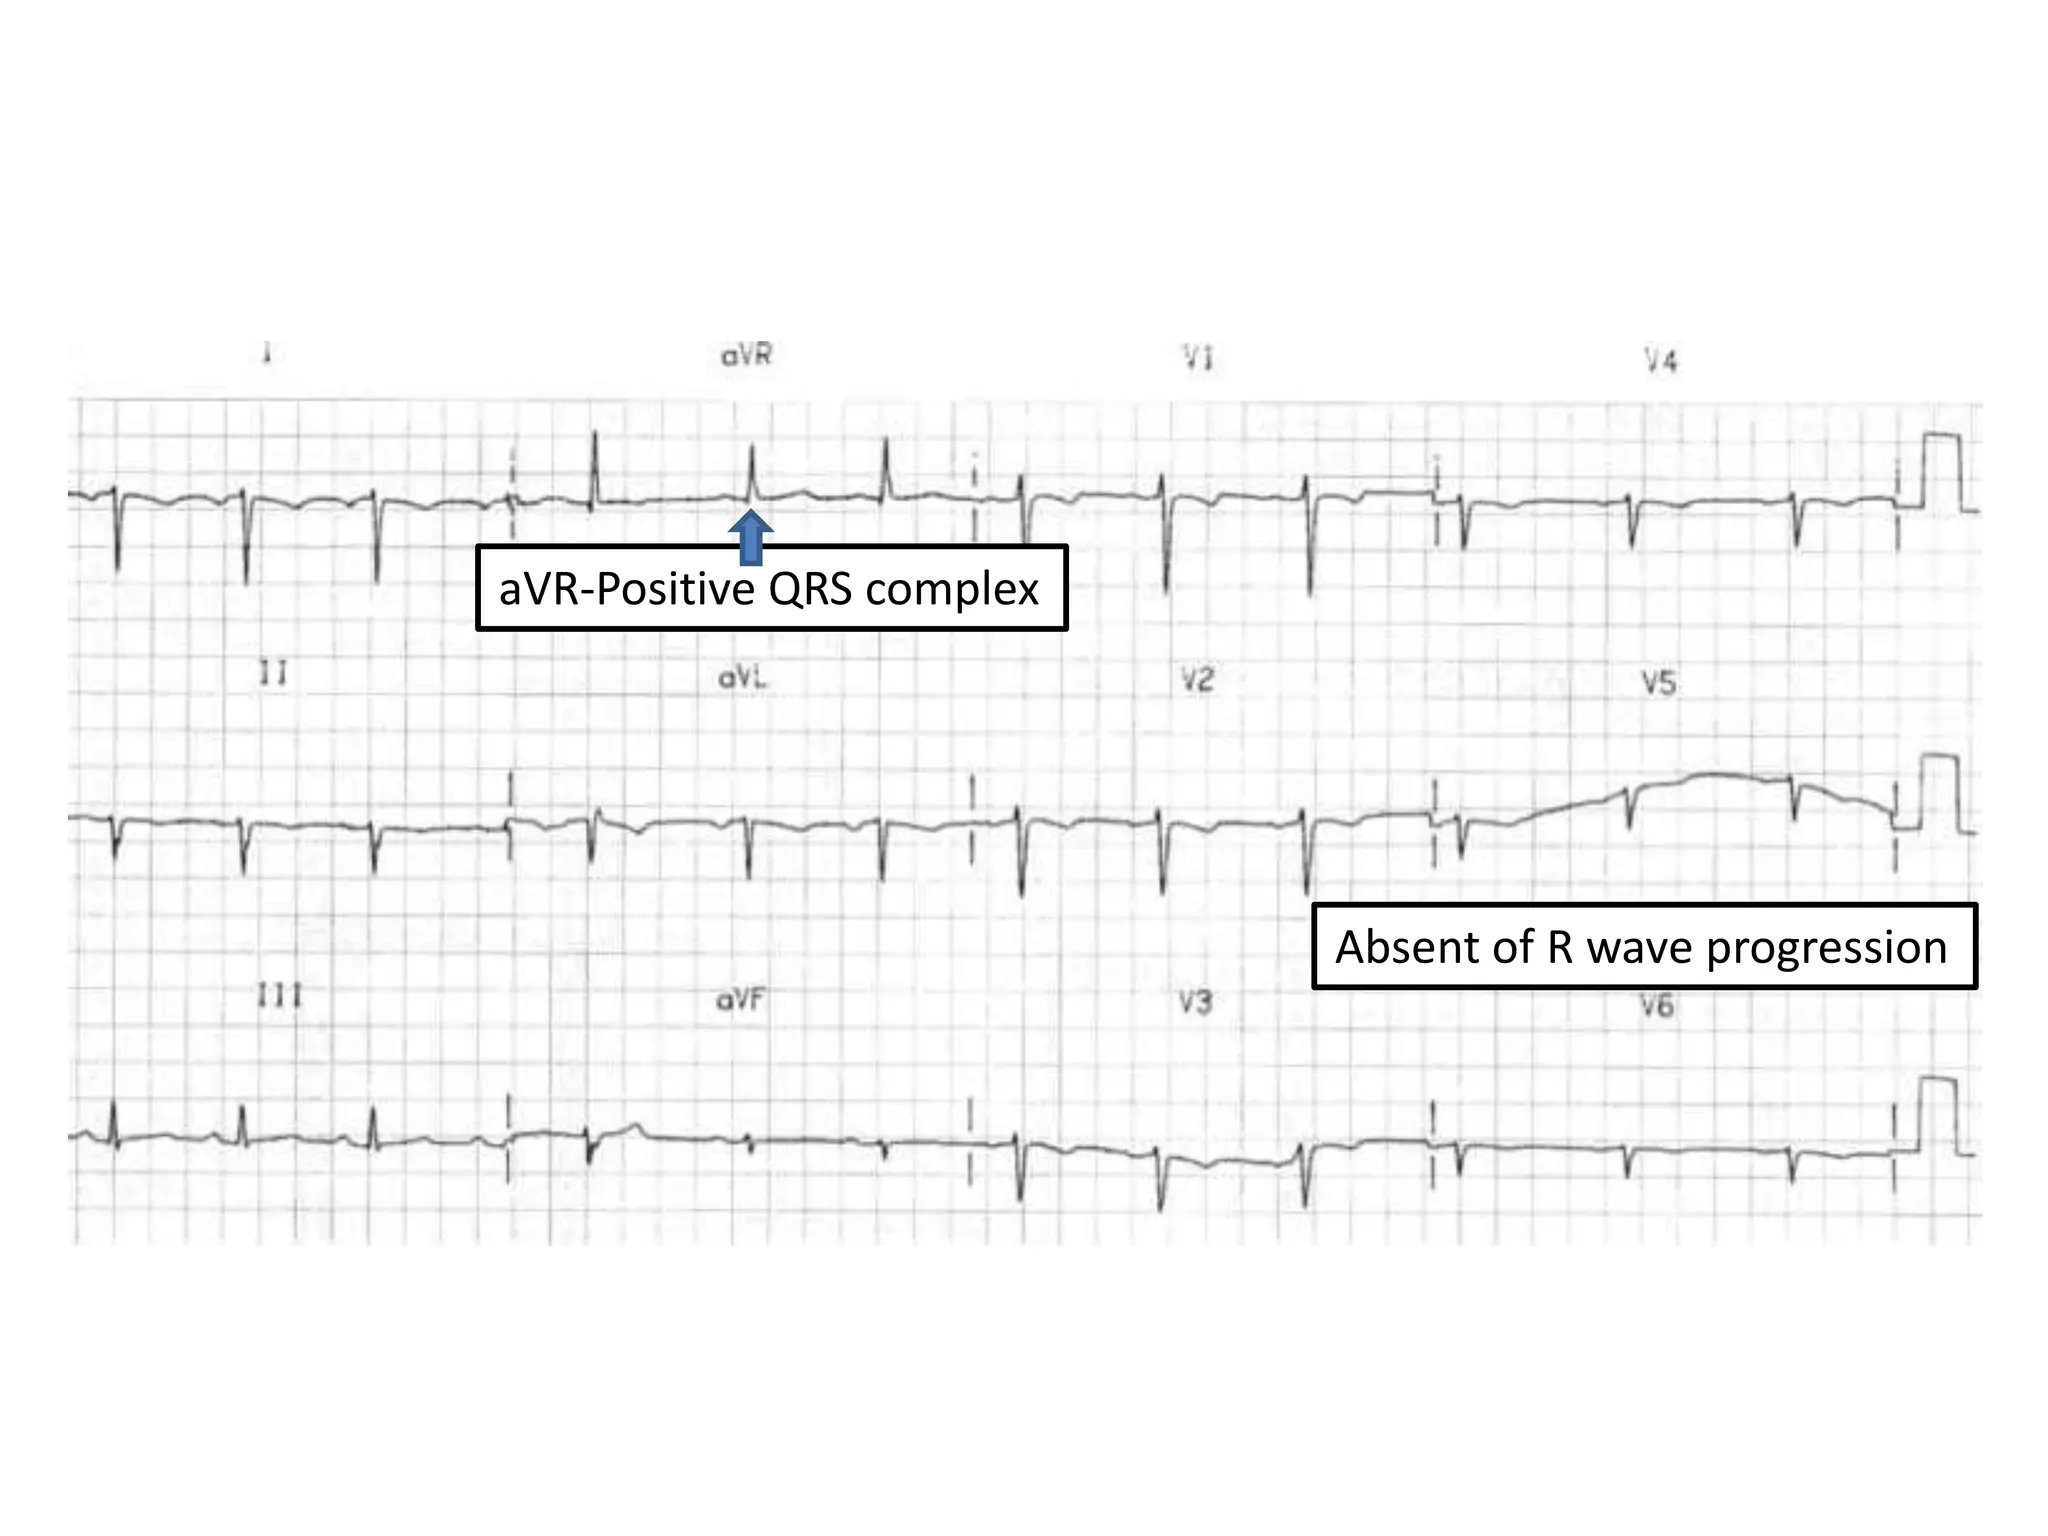

DEXTROCARDIA

• Right axis deviation

• Positive QRS complexes in aVR

• Absent R-wave progression in the chest leads

,dominant S waves throughout

aVR-Positive QRS complex

Absent of R wave progression